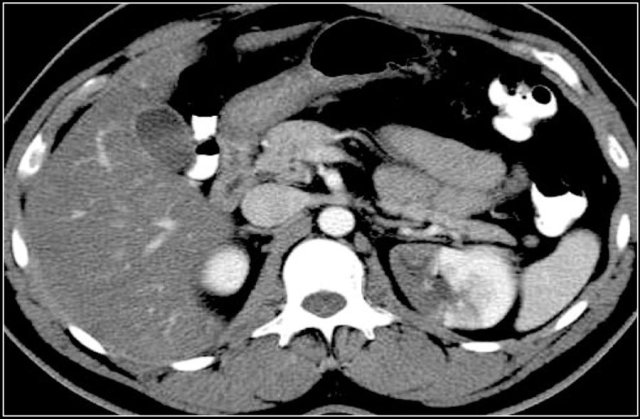

Prominent columns of Bertin, bulging of the renal contour and focal renal hypertrophy can look like a renal mass on ultrasound, unenhanced images and CT in the nephrogenic phase.

In the corticomedullary phase the normal corticomedullary pattern in these pseudotumors can be appreciated, distinguishing them from real lesions.

Suspected renal mass of the left kidney on ultrasound.

CT shows a bulging of the left renal contour, commonly referred to as a dromedary hump.

Here is another case.

In the nephrogenic phase one could argue there is a lesion in the left kidney.

In the corticomedullary phase however it is clear that this is a pseudotumor.